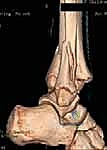

- الكسر ثلاثي المستويات (Triplane Fracture): كسر شديد التعقيد يمر عبر ثلاثة مستويات مختلفة (سهمي، إكليلي، وعرضي). يظهر في الأشعة الأمامية ككسر سالتر-هاريس من النوع الثالث، وفي الأشعة الجانبية ككسر من النوع الثاني. يتطلب هذا الكسر دائمًا فحصًا مقطعيًا (CT Scan) لتقييمه بشكل صحيح.

- الأشعة المقطعية ثلاثية الأبعاد (3D CT Scan): تُعد ضرورة حتمية في حالات كسور تيلوكس والكسور ثلاثية المستويات، أو أي كسر يمتد داخل المفصل. توفر الأشعة المقطعية خريطة دقيقة لحجم القطع العظمية ومقدار التباعد (Displacement)، مما يساعد في التخطيط الجراحي المسبق.